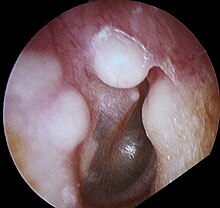

Osteoma (plural: "osteomata" or "osteomas"), is a non-cancerous bone tumor, a type osteogenic tumor, where a new piece of bone typically grows on another piece of bone, usually on the skull and near the sinuses.[1][2] Often there are no symptoms as the tumor grows slowly, but there may be pain, headache, blocked paranasal sinuses or local swelling.[1] It may present with sinusitis.[3]

Medical imaging such as X-ray, CT scan and MRI show dense, clearly defined, round white tumors attached to bone.[1] They can be left alone if not troubling, and surgically cut out if pressure symptoms.[1] The surgery may be possible through the nose, without making a large cut.[3]

Medical imaging such as X-ray, CT scan and MRI show dense, clearly defined, round white tumors attached to bone.[1] They may be diagnosed when having medical imaging for another reason.[3] Osteomas of the paranasal sinuses and skull base can be diagnosed using CT-scan without intravenous contrast, allowing its size and relation to nearby important structures to be assessed.[3] A biopsy is not usually required.[3]